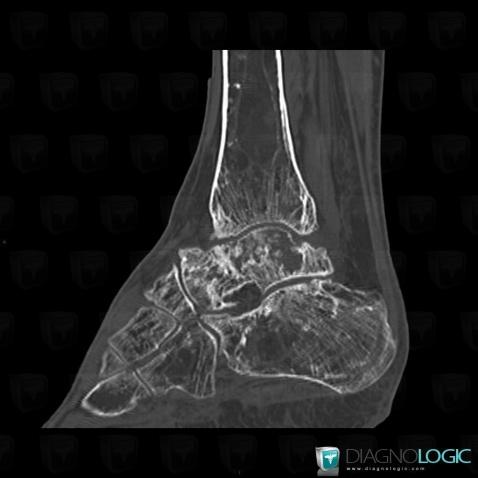

Avascular necrosis, Tibia - Distal part, Calcaneus, CT

Here is the specific information in the key image above:

- Diagnosis Gaucher disease, Location(s) Tibia - Distal part, with gamuts Mulltiple osteolysis

- Diagnosis Avascular necrosis, Location(s) Calcaneus, with gamuts Lucent lesion in foot, Osteolytic lesion of calcaneusTibia - Distal part, with gamuts Well-defined osteolysis

Avascular necrosis, Talus, CT

- Diagnosis Avascular necrosis, Location(s) Talus, with gamuts Lucent lesion in foot